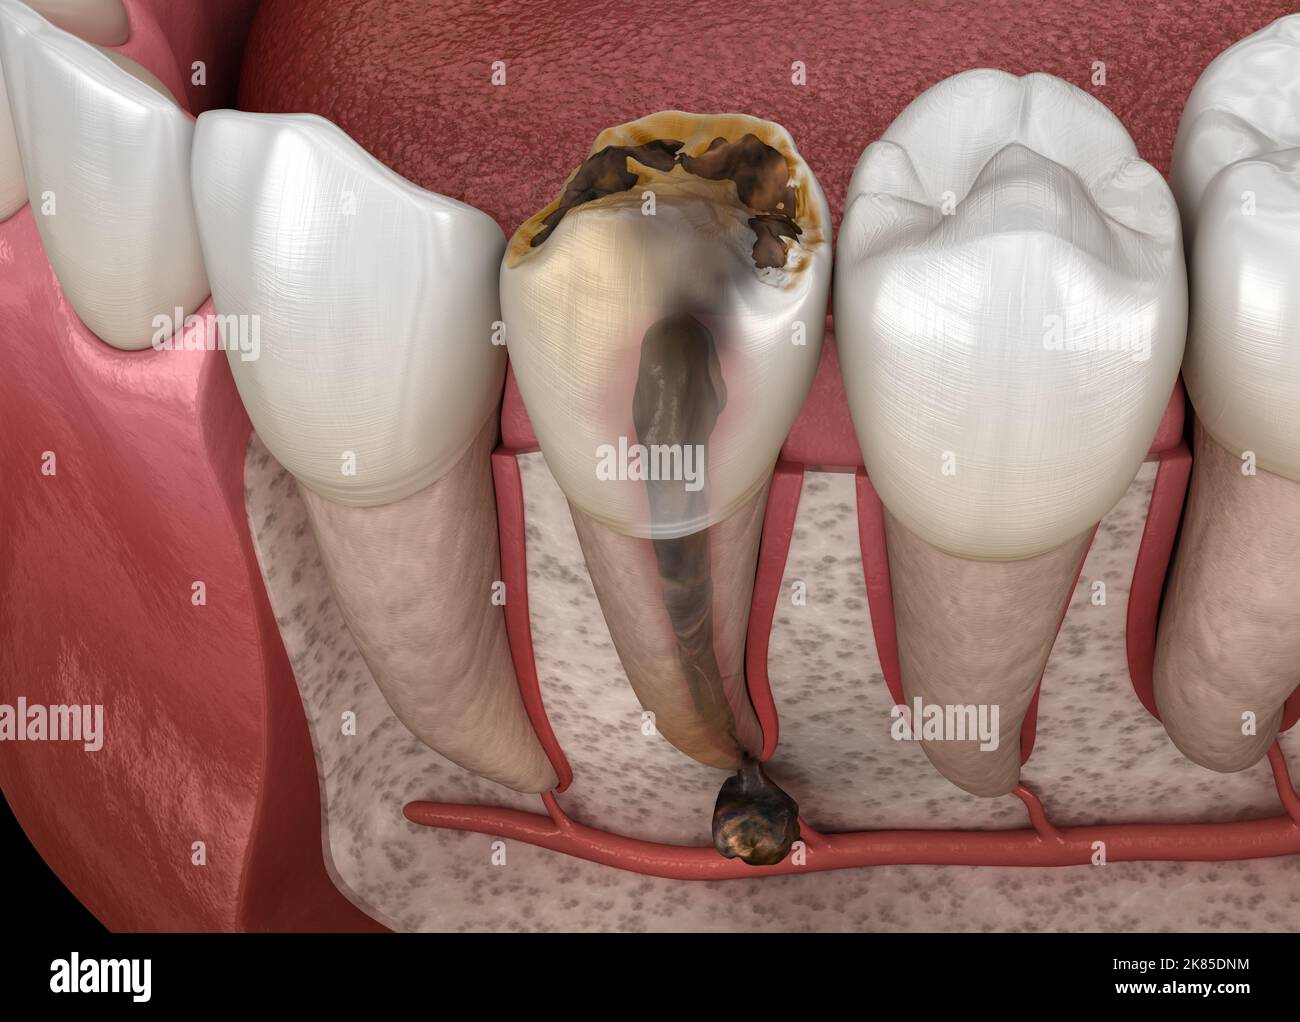

From www.alamy.com

Periostitis tooth Lump on Gum Above Tooth. Medically accurate dental Periostitis Jaw — garre’s osteomyelitis of the jaw refers to a particular type of pathological change and clinical manifestation of chronic marginal. — proliferative periostitis is a rare disease, and represents new bone formation with periosteal reaction. In more detail, periostitis is an inflammation of the periosteum. What are the clinical and histologic features of proliferative periostitis? What are the. Periostitis Jaw.